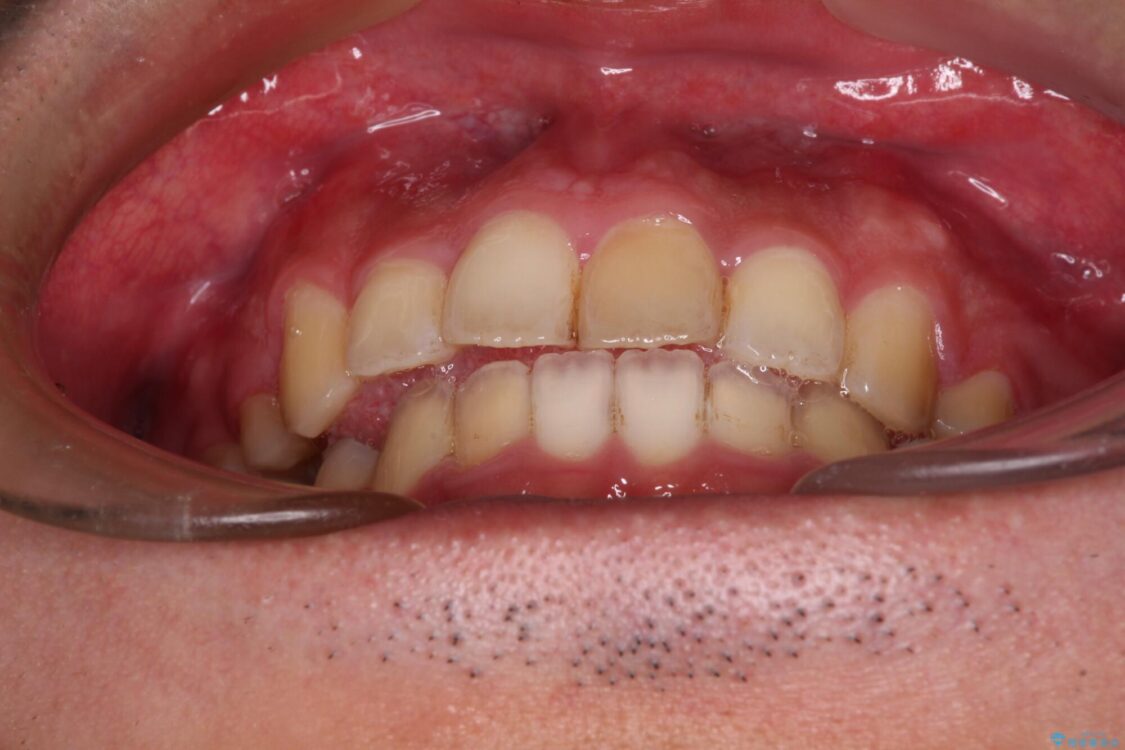

治療前

• 後戻りでデコボコの前歯 インビザライン矯正治療 治療前画像